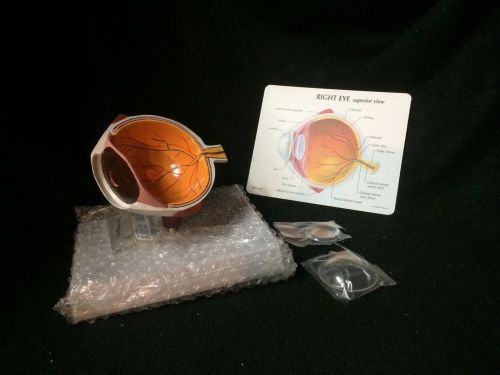

Antique Vintage Clay Adams - Human Eye Anatomical Eyeball Model

GPI #2750 Right Human Eye Cutaway Eyeball Section Anatomical Model